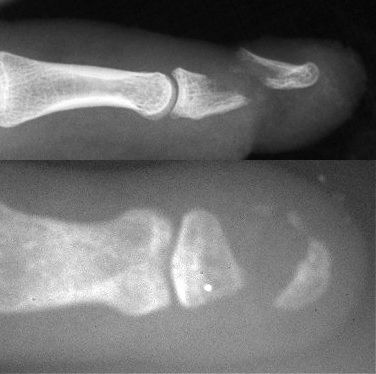

Figure Legend: Distal phalanx nonunions

are uncommon, and usually follow open injuries. Risk factors include inadequate

reduction of displaced fragments, soft tissue interposition or bone loss,

including bone loss due to surgical debridement. The top image shows the

type of acute displaced fracture which is best treated with internal fixation.

The bottom image shows an established nonunion following bone debridement

and wound closure. Most fractures which require bone debridement would

benefit from internal fixation. Late salvage of distal phalanx nonunions

is technically demanding and requires precision bone grafting technique.